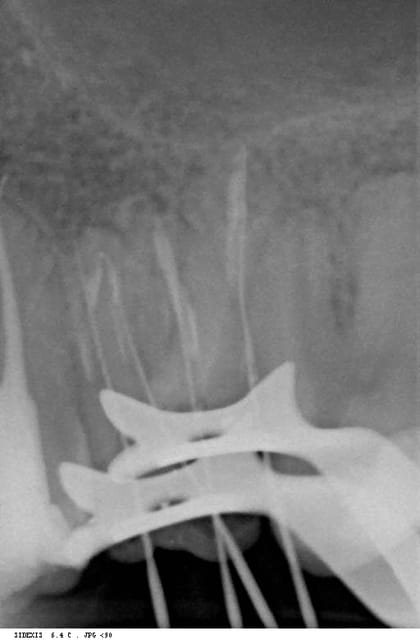

la perfo est en effet intracanalaire, elle démarre pile au niveau de la courbure apicale.

je regarde à nouveau cette radio,on voit la perf en distal,qui a suivi un chemin rectiligne plutot que de suivre la courbe de la dent,mais pourquoi cette autre broche entre les deux molaires?,ce n'est pas un canal,si je lis bien cette radio?

si la lime 1 est la plus a droite de laRX, le distal etantà G c'est la quelle qui te tracasse? la 1? la 4? tu situes la perfo où?

l'interrogation vient du cone le plus a droite de la radio! la perf indiquée par un rond!

non annie, il y a une perf, elle est sur le mv1, c'est tout.

annie, ou vois-tu une broche entre deux molaires?

Sur ta radio la broche a l'extrème droite ,

c'est le canal palatin, annie. c'est le canal palatin.

regarde bien cette broche a l'interieur de l'ovale du clamp,il n'y a pas de dent autour!

voilà une radio avec une autre incidence: tu vois le canal palatin? tu vois l'obturation dedans? non?